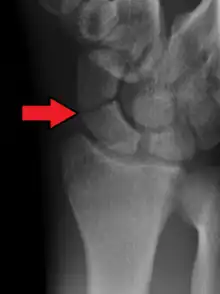

Radiolucency around a 12 days old scaphoid fracture that was initially barely visible.[13]